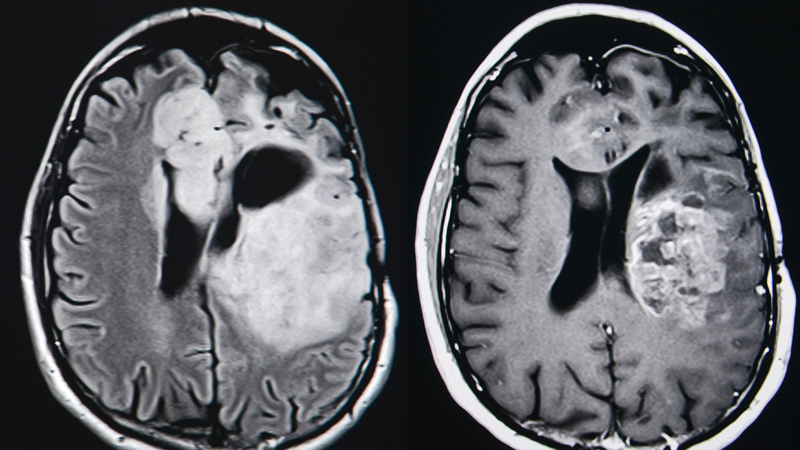

A brain tumor is a collection of abnormal cells in your brain. The tumor may be primary (starting in your brain). Or, the tumor may be metastatic (cancer that started in another place in your body and spread to your brain).

Brain tumors can cause serious damage, even if they are benign. The degree of damage depends upon the type, size and location of the tumor.

Advanced Diagnosis and Treatment

At Northwestern Memorial Hospital, you will have access to the latest imaging and diagnostic tools available, as well as the most advanced surgical and non-surgical treatment options. Our neuro-oncology team is one of the largest in the country, and includes world-renowned experts. Our radiation oncologists offer the latest radiation technologies, including radiosurgery and proton beam therapy. We perform more brain and spine tumor surgeries than any other health system in Illinois.